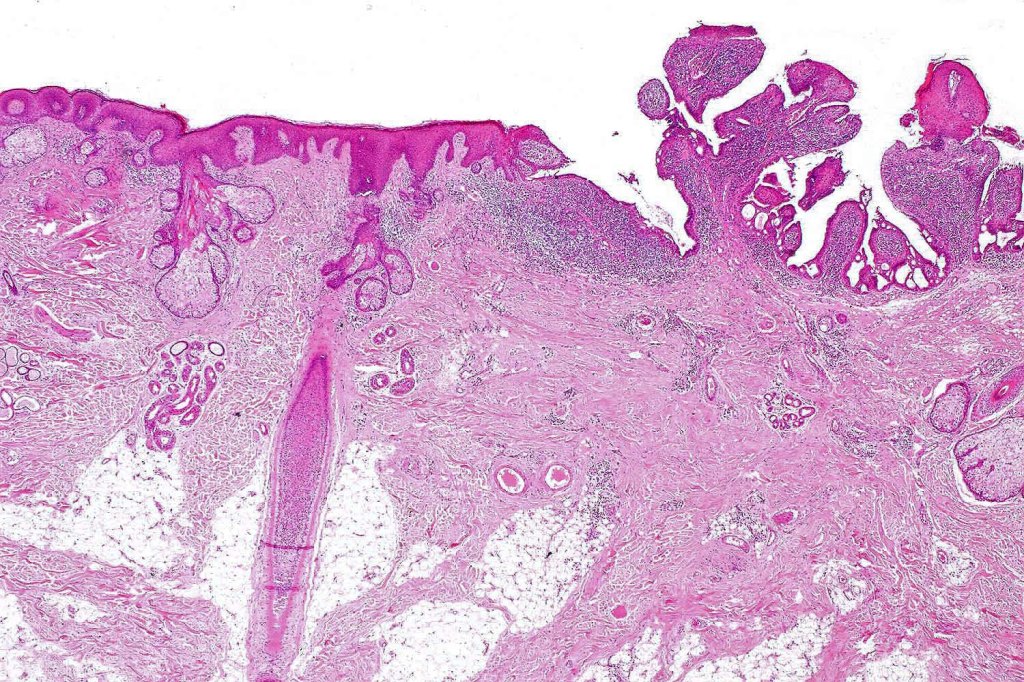

•Hamartoma characterized by abnormalities of epidermis, hair follicles, sebaceous glands, apocrine sweat glands & connective tissue

•Epidermis often papillomatous

•High, increased hyperplastic, sebaceous glands with openings onto the surface epithelium (in. old lesions, they may be absent)

•Reduced hair follicles

•Excessive numbers of apocrine glands

•May be complicated by a wide range of tumors (which are often multiple) including trichilemmoma, trichoblastoma, SCAP, sebaceous tumors, sweat gland tumors, melanocytic nevi & rarely by malignant tumors including BCC, SCC, melanoma, trichilemmal carcinoma, apocrine carcinoma & microcystic adnexal carcinoma